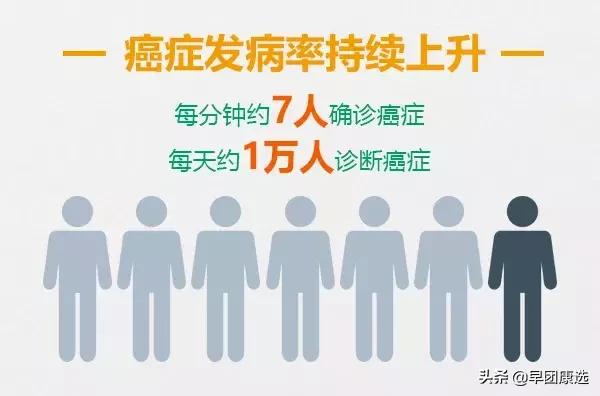

国家癌症中心发布的中国最新癌症数据《2017中国肿瘤登记年报》显示:

在我国平均每天约1万人、 每分钟约7人确诊患癌。如果一个人活到85岁,那么他的患癌风险就有36%。